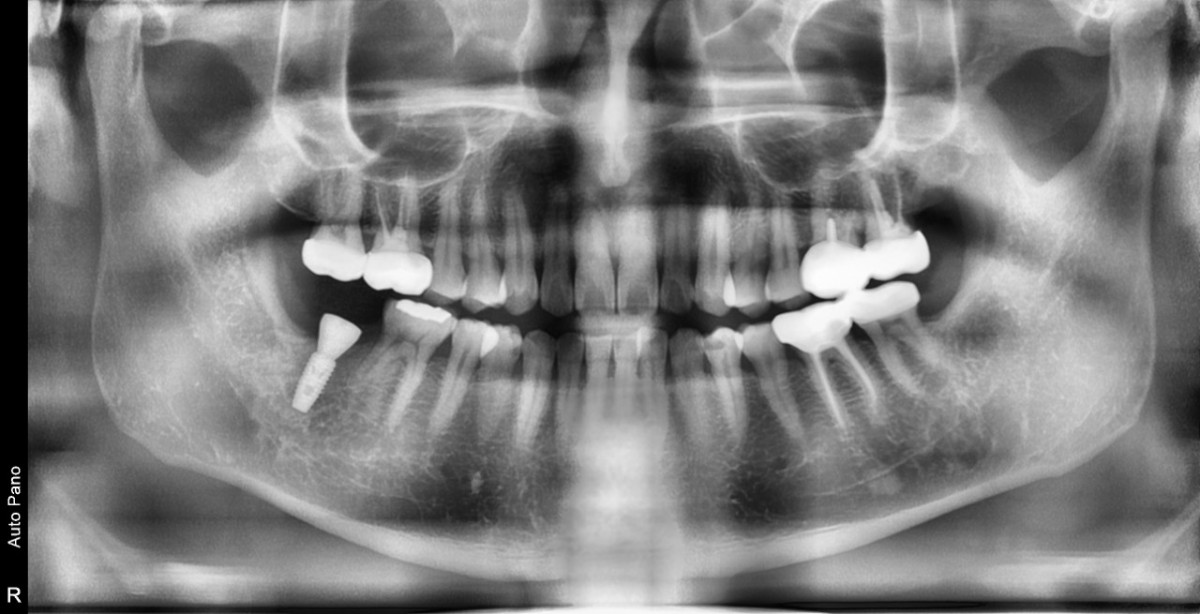

Single implant (staged) Arum NB1, f/u

A 47-year-old male patient had a crown with an ill-fitting margin and crack-tooth syndrome in the lower 2nd molar. No systemic issue.

▲torque value after insertion

▲Arum Dentistry NB1 5*10